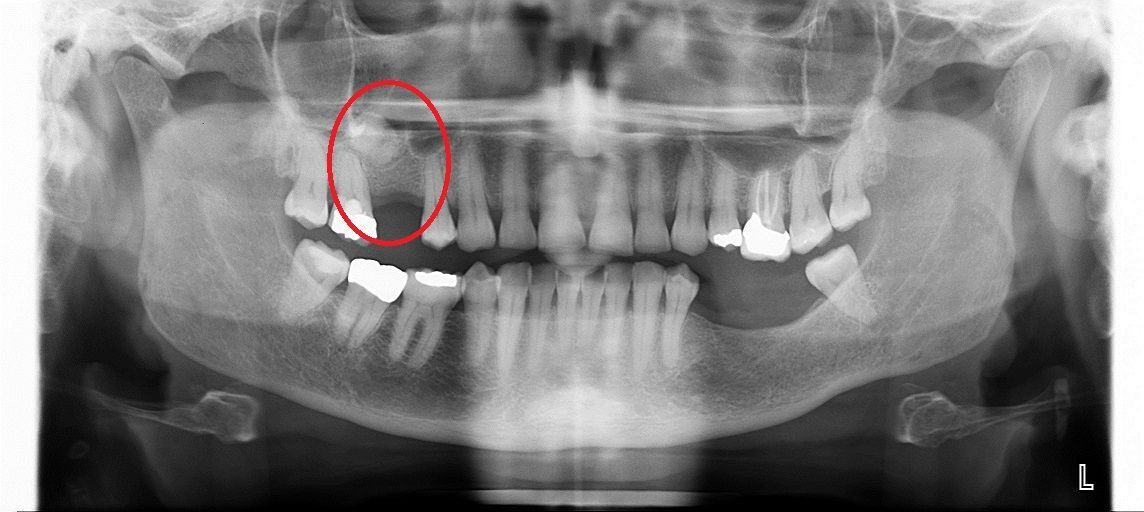

Синус лифтинг

После удаления зуба из-за отсутствия необходимой нагрузки на челюсть, кость в пустующем месте атрофируется. В этом случае перед имплантацией необходимо восполнить объем костной ткани.

Разновидность костной пластики направленной на увеличение объема костной ткани верхней челюсти в районе гайморовых пазух.

Открытый синус лифтинг

Открытый синус-лифтинг применяется, когда для установки имплантата не хватает более 3 мм костной ткани. При проведении этой операции имплантация в ряде случаев возможна только после полного восстановления кости челюсти.

• до синус-лифтинга

• после синус-лифтинга

• после установки имплантатов в верхнюю челюсть